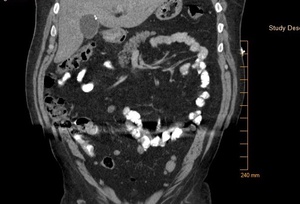

His laboratory values were significant for elevated total and direct bilirubin (22.4 and 15.9 mg/dl). Additional lab values include – an AST (137 U/L) and ALT (232 U/L), and an abnormally elevated Lipid panel with LDL (263 mg/dl), triglyceride (357 mg/dl), and total cholesterol (346 mg/dl). On day three of admission, the patient underwent an endoscopic retrograde cholangiopancreatography (ERCP) with findings significant for multiple gallstones in the common bile duct (Fig. 1 - 4) consistent with Mirizzi syndrome.

On the ERCP, patient had outpouching in the cystic duct. A stent was placed in the common bile duct (CBD). The patient’s direct bilirubin decreased from 7.4 mg/dl to 5.9 mg/dl. The patient was scheduled to follow up with gastroenterologist in two to three weeks for the removal of the CBD stent, and he improved markedly post-stent placement. He was asymptomatic on discharge.